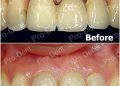

止鼾案例-配戴中-1

止鼾案例-配戴中-2

止鼾案例-配戴後